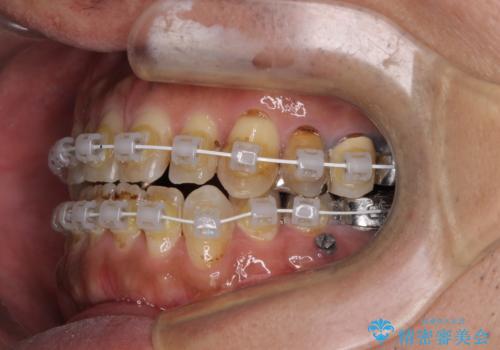

- 審美装置

- 1年11ヶ月

- 10-30回

前歯の反対咬合が改善する過程では、奥歯が咬みにくくなるため、食事では辛い思いをされていたようです。